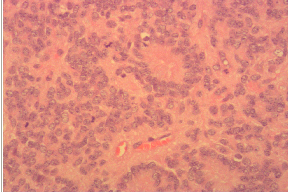

术前诊断:四脑室占位性病变:室管膜瘤可能性大;梗阻性脑积水 手术难点在于对后循环及脑干的保护。 考虑患者颅内压力高,先行“左侧脑室穿刺外引流”。患者右侧卧,选左侧脑室三角部穿刺点穿入,粗测脑室内压力250mmHg。选择左枕部倒L形切口,枕外隆突上1cm水平左延8cm,向下沿中线至第二颈椎棘突。沿正中白线进入,暴露枕骨至枕大孔边缘,暴露左侧枕骨骨瓣。咬除枕骨鳞部,骨窗上近横窦下缘,下至枕骨大孔,约4cm*5cm大小。打开引流管,硬膜张力下降后沿骨窗边缘放射状剪开硬膜,悬吊后于小脑半球中间血管较少处造瘘,深入约2.5cm见肿瘤。灰白色,鱼肉状,约5cm*4cm*4cm大小,质软稍脆,部分病灶伴钙化。肿瘤基底位于四脑室顶壁,外侧突入左侧桥小脑角区、桥臂下方,腹侧压迫脑干并有部分粘连。显微镜下分块全切肿瘤。止血、关颅。枕骨大孔处咬除骨质扩大至3cm,并咬除枕骨鳞部下方部分骨质形成减压窗。其余骨瓣回纳固定。